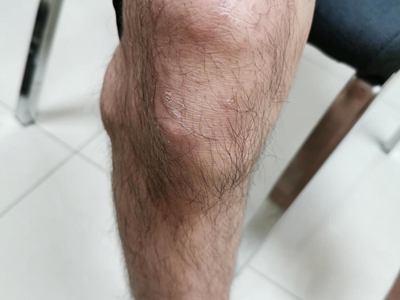

痛风性关节炎好发于40岁以上男性,多见于第一跖趾关节,也可发生于其他较大关节,如踝部关节、膝关节、手指关节等,表现为突然出现的关节肿胀和剧痛,受累关节及其周围软组织明显发红、发热和肿胀,剧痛难忍,以及关节活动受限,伴有痛风石的形成和慢性关节变形。